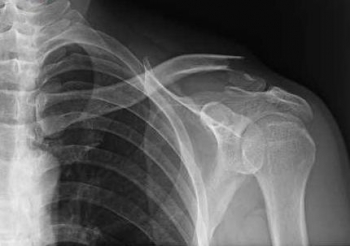

今日、ご紹介するのは、鎖骨の骨折についてご紹介していきたいと思います。

鎖骨は、胸部の上部に左右にあり、胸骨と肩甲骨を連結させて肩構造を支持しています。

内側端で胸骨と関節し(胸鎖関節)、外側端で肩甲骨と関節し(肩鎖関節)をなします。

鎖骨骨折

鎖骨骨折は、とても発生頻度が高く、転倒し、肩・肘・手を突いた際に介達外力によるものが多いです。

鎖骨でもっとも骨折しやすい場所は、力学的に弱い中外1/3の境界部です。

直達外力での骨折はまれですが、発生した際、外1/3部(外端部)に発生が多いです。

鎖骨骨折は、固定が難しいため、現在では手術でプレートなどで固定する場合が多くなりました。